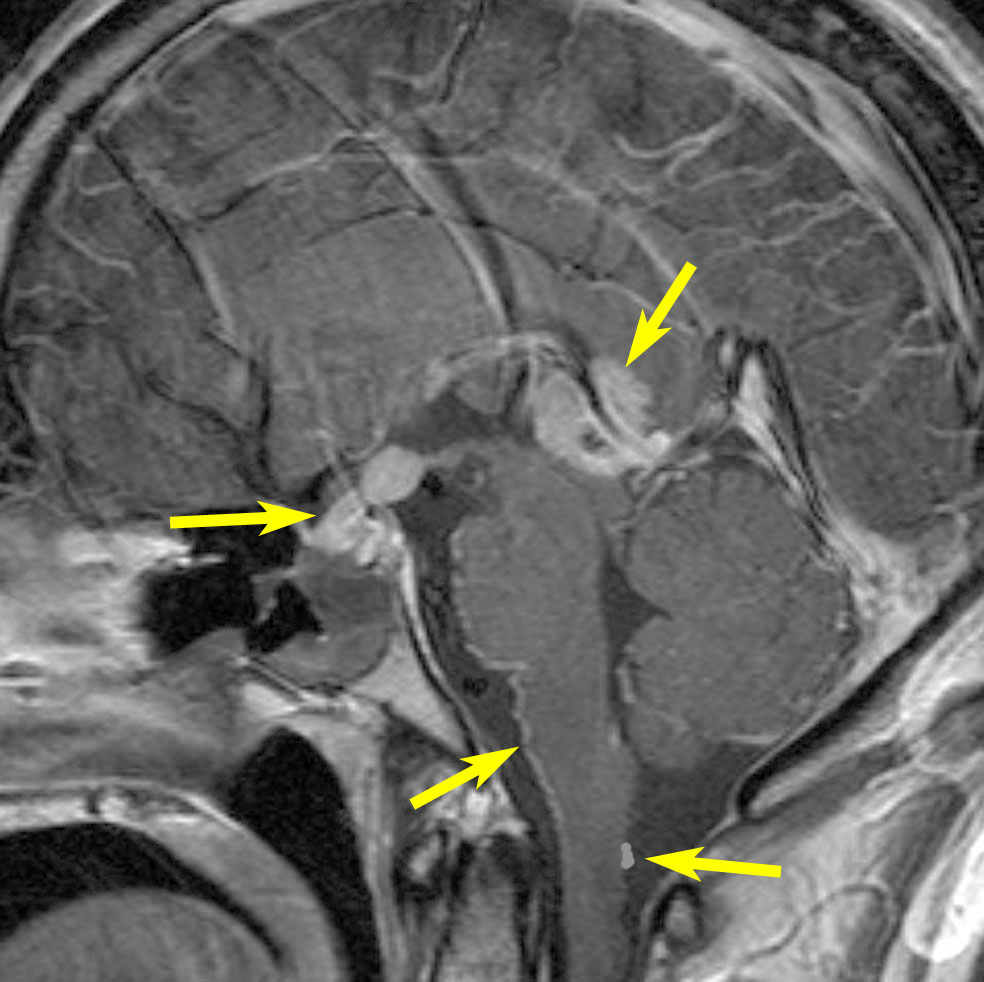

20歳くらいから尿崩症があり,2年後に汎下垂体機能低下症と軽度の認知機能低下を生じました。脳室壁と松果体,神経下垂体にジャーミノーマが広がっているのですが,脊髄背面と脳幹部の周囲にも腫瘍結節が見られました。脳室上衣以外の部位に腫瘍があるので,播種を疑いました。ジャーミノーマの播種というのは実際にはとても珍しくてなかなかみないものです。HCGは軽度の上昇,鼻孔から下垂体部分を生検して病理確定診断して,化学療法と脳脊髄照射 25.2Gy をしました。腫瘍は1コース目の化学療法でほとんど消失したので,他の組織型の悪性混合性胚細胞腫瘍ではないと考えられます。

3年後に脳室壁に再発しました。脳梁と脳弓の機能低下があり認知機能低下は高度でした。松果体と神経下垂体には再発はありません。

この再発の原因には,側脳室前角の先端部が照射野に十分含まれなかったという疑念があります。